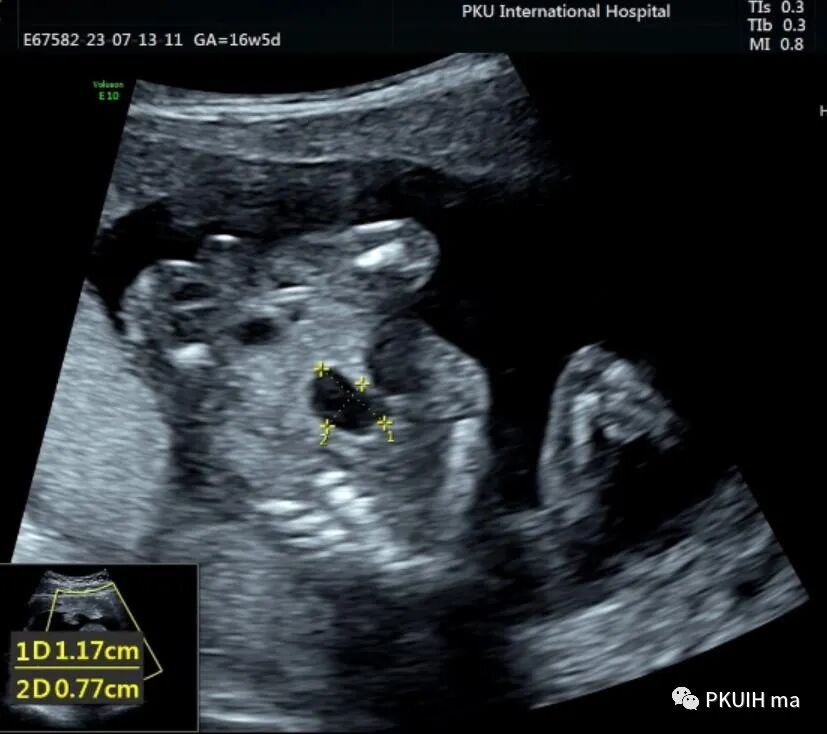

胎儿中腹部见一囊性包块,大小约1.2x1.0x0.8cm,边界清,形态规则,内透声好。囊肿位于脊柱前方、胆囊后方、门静脉窦旁,与后肾接近

仔细观察囊肿壁好像不完整,周边见微小管道回声与囊肿相通

由于囊肿位于胆囊后方、肝下方、门静脉窦旁,随考虑为胆总管囊肿